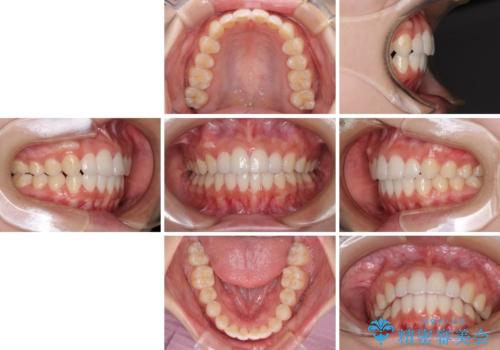

前歯のデコボコと突出感 インビザラインで改善

骨格的な左右差があったため、上下の正中を合わせることは困難かと思われましたが、何とか合わせることができました。

一方、骨格の差は改善できないため、奥歯の咬み合わせに物足りなさを感じました。

奥歯の咬み合わせによる不自由はなく、患者様に大変満足していただきました。